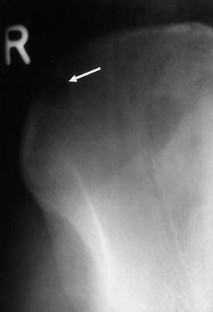

Spontaneous malignant transformation of conventional giant cell tumor (GCT) of bone is exceedingly rare. We report on a case of GCT of the iliac crest in a 35-year-old woman with malignant change into a high-grade osteosarcoma 10 years after the first appearance of GCT on a radiograph. Since the patient refused therapy for personal reasons the tumor remained untreated until sarcomatous transformation occurred. Image cytometry showed DNA aneuploidy and a suspiciously high 2c deviation index (2cDI) in the primary bone lesion. A thorough review of the world literature revealed only seven fully documented cases of secondary malignant GCT which matched the definition of a “sarcomatous growth that occurs at the site of a previously documented benign giant cell tumor” and not treated by radiotherapy. These cases as well as the current one suggest that a spontaneous secondary malignant GCT presents as a frankly sarcomatous tumor in the form of an osteosarcoma or malignant fibrous histiocytoma. It usually appears at sites of typical GCTs—often without any recurrent intermediate state—and is diagnosed 3 or more years after the primary bone lesion. The prognosis is poor.

Fig. 2